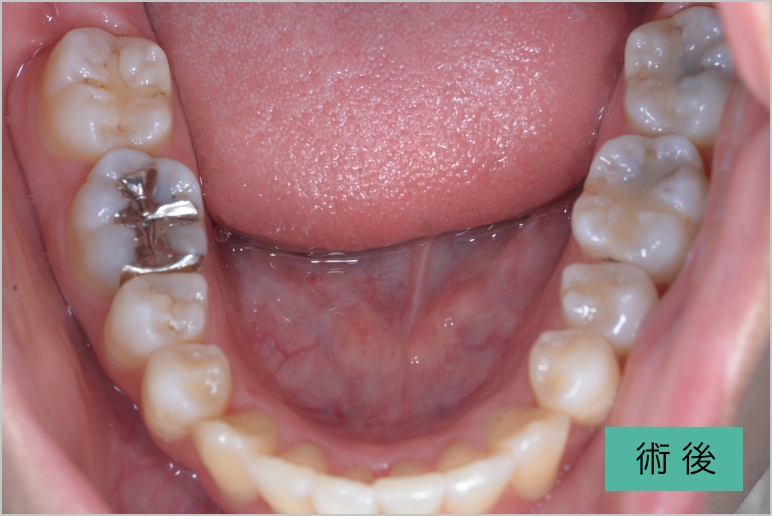

インビザライン①

| 治療内容 | 歯並びがコンプレックスで来院 左上下顎両側智歯の抜歯を行い、インビザラインでマウスピース矯正を行う 右下1番は歯肉退縮がみられた為根面被覆を行う マウスピース矯正終了後はリテーナーを使用 |

|---|---|

| 治療期間・回数 | 約2年半、30回 |

| 費用(税込) | ¥880,000(マウスピース矯正) ※自由診療 |

| リスク・副作用 | 歯肉退縮、知覚過敏、後戻り |